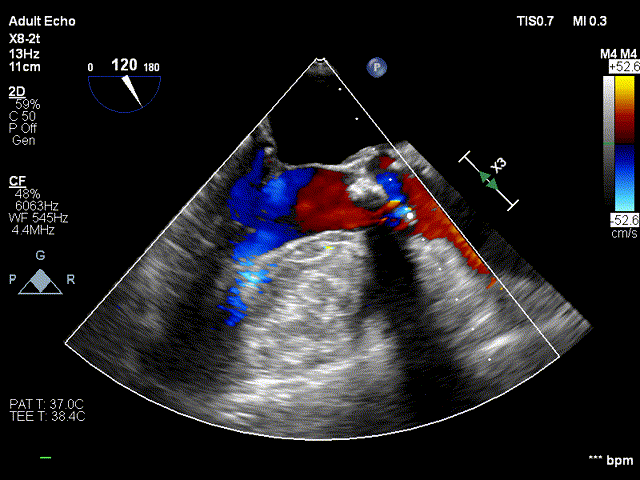

术后超声:

术后超声-短轴切面

术后超声-长轴切面

随着TAVR技术在国内的普及,主动脉瓣狭窄患者有了更多的治疗选择。本例病人为主动脉瓣重度狭窄伴轻度反流,手术指征明确,患者明确拒绝外科手术,术前解剖形态评估适宜行TAVR手术,有TAVR手术指征。经罗骏、崔凯教授团队的综合评估,结合心内科、心外科、超声等多学科团队的讨论意见,最终决定为患者施行TAVR手术治疗。手术过程中,TaurusElite经导管主动脉瓣输送系统在保持回收性能稳定的同时兼具优异的柔顺性,顺利完成过弓、跨瓣操作。其次,针对本例患者钙化较重、瓣叶局部粘连的特点,TaurusElite瓣膜高密度流入端设计提供了足够的径向支撑力,保证了瓣膜的锚定力;低密度流出端的设计也兼具柔顺性,能帮助术者更好的完成过弓与跨瓣操作。此外,TaurusElite瓣膜内外双裙边设计能有效减少瓣周漏,适度的收腰既能保证足够的有效瓣口面积,又降低了冠脉阻挡风险。最后,面对临床复杂的解剖结构特点,瓣膜释放过程中可能出现瓣膜下滑或上跳的风险,增加了术中释放瓣膜的难度;而TaurusElite瓣膜系统具有多次原位回收、回收后可重新跨瓣等设计特点,让术者释放过程中更有信心,能降低手术风险,减少并发症的产生,从而让患者得到更好的预后。本例患者术中的情况验证了术前CT分析的准确性,最终瓣膜释放位置良好,冠脉血流灌注正常,术后压差明显降低,术后跨瓣压差从101mmHg降至2mmHg,仅有微少量瓣周漏。术后病人恢复良好,各项生命体征平稳,手术效果十分优异。